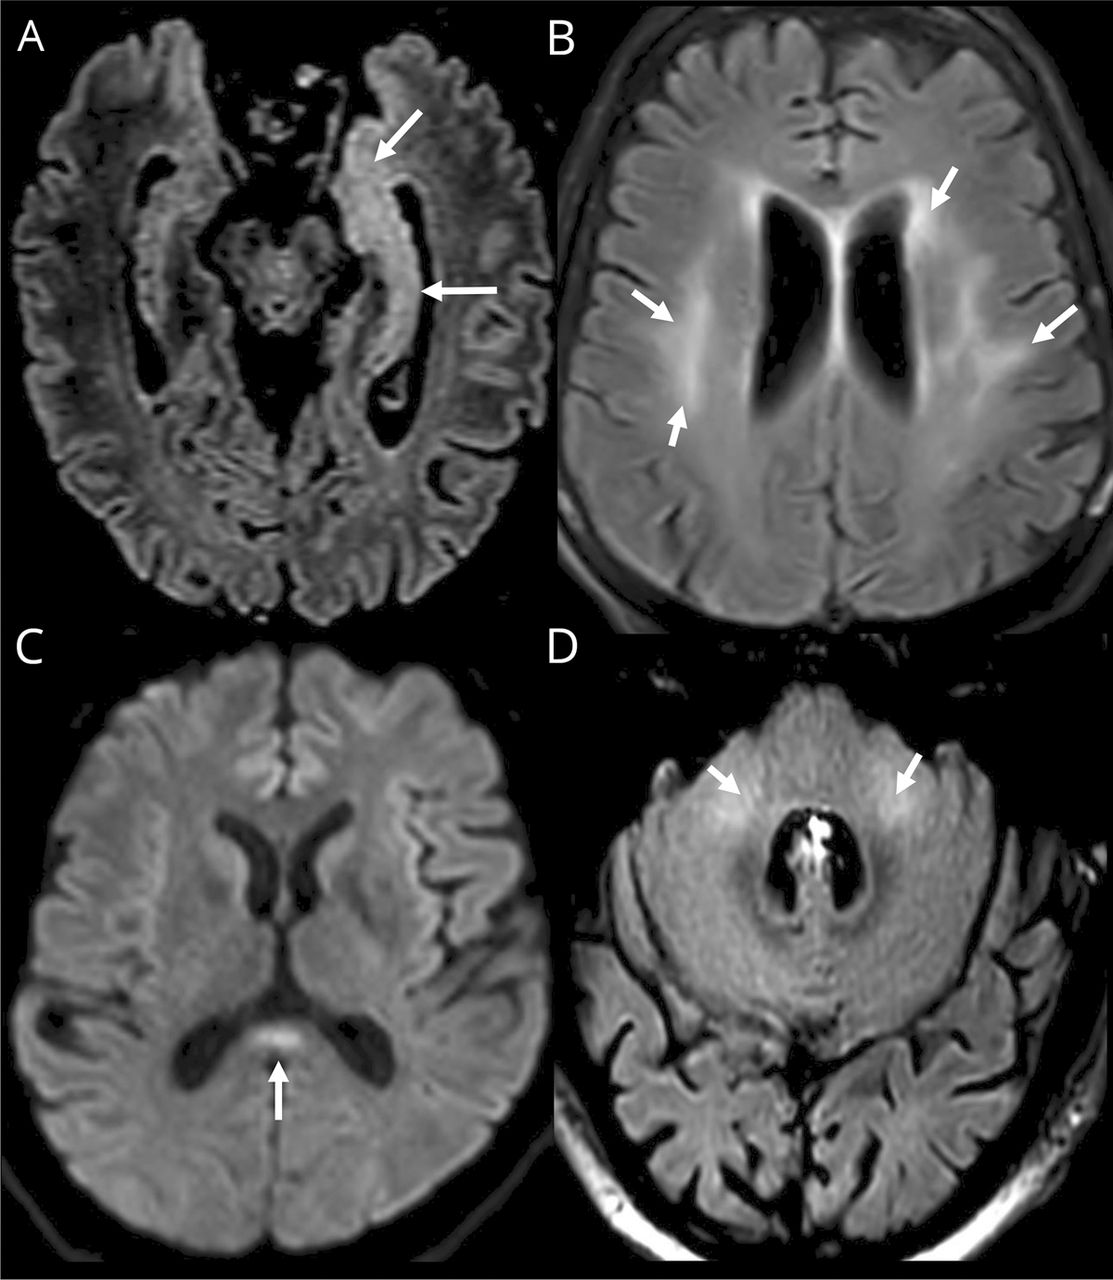

Ischemic strokes (27%) (figure e-1, available from Dryad,doi.org/10.5061/dryad.w9ghx3fm7), LME (17%) (figure 1), and encephalitis (13%) (figures 2and3and figure e-2, available from Dryad) were the most frequent neuroimaging findings. LME was seen on both postcontrast T1-weighted and FLAIR sequences and was even better visualized when delayed postcontrast FLAIR was performed. These signal abnormalities were not present on precontrast T1 or FLAIR images.

(A, B, D) Axial fluid-attenuated inversion recovery (FLAIR) and (C) diffusion-weighted MRIs. (A) Man 56 years of age: left hippocampus and amygdala FLAIR hyperintensity. (B) Woman 71 years of age: periventricular and subcortical white matter FLAIR confluent hyperintensities. (C) Man 55 years of age: corpus callosum splenium diffusion hyperintensity. (D) Man 64 years of age: FLAIR middle cerebellar peduncle hyperintensity.

Among the 8 encephalitis, 2 cases of limbic encephalitis, 2 cases of radiologic acute hemorrhagic necrotizing encephalopathy, 2 cases of miscellaneous encephalitis, 1 case of radiologic ADEM, and 1 case of CLOCC were described.